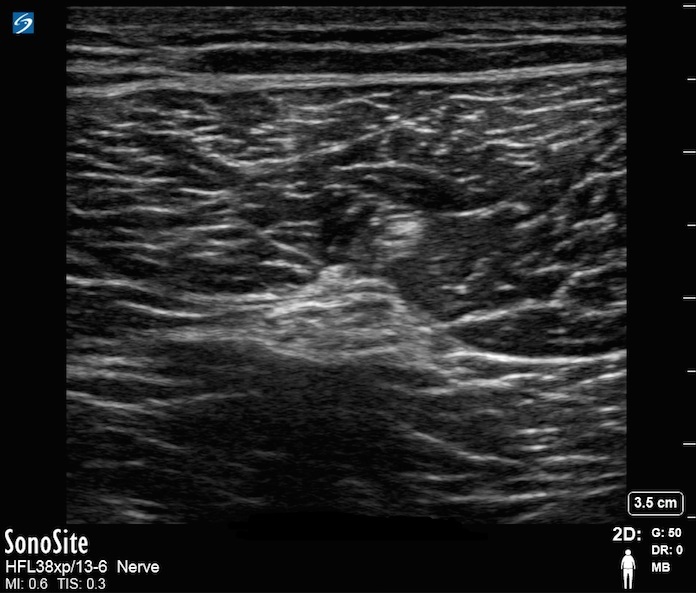

Image : Nerf sciatique poplité